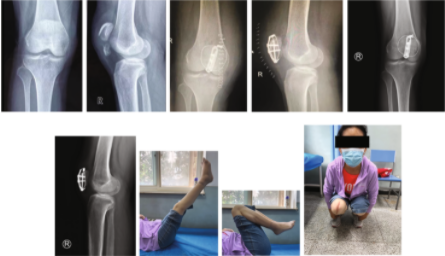

图3. 对照组和实验组患者复位前后的比较。

a - f : 38岁,男性,入院前3小时因摔伤导致骨折入院。a-b术前CT检查矢状面。c-d术前冠状面CT检查。e-f术后x线片。

g-l:一名65岁女性,入院前5小时因跌倒导致骨折。g-h术前矢状面CT检查。i-j术前冠状面CT检查。k-l术后x线片。

扎骨针怎么装髌骨下极粉碎骨折怎么办?7种固定技术详解与术式选择_https://www.jmylbn.com_新闻资讯_第27张

图4. 对照组和实验组患者术后骨折愈合情况比较a-d。患者男,42岁,入院前4 h因跌倒致骨折入院。

a.术前x线侧位片

b.术后x线侧位片

c.术后12周随访x线侧位片。患者女,38岁,入院前3 h因跌倒致骨折入院

d.术前矢状面CT检查

e.术后x线侧位片

f.术后12周随访x线侧位片